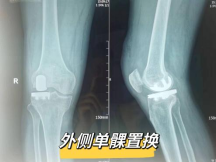

保髋、保膝手术:股骨头坏死髓心减压术、胫骨高位截骨矫形术、内外侧单髁置换术、关节镜下关节清理术。